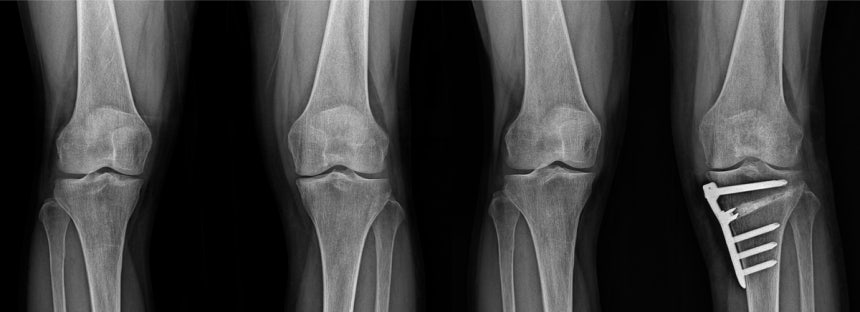

손상이 내측에 국한되고 O다리가 동반된 비교적 젊은 환자라면 인공관절보다 자기 관절을 보존할 수 있는 근위경골절골술이 우선 고려된다.

내측 관절염이 2~3기이고, 가쪽 관절과 인대가 비교적 보존된 젊은 환자에게 적합하다. 장점은 자기 관절을 보존해 운동 범위를 유지하고, 러닝·테니스 복귀가 가능하며, 관절염 진행 속도를 늦춰 인공관절 시기를 미룰 수 있다는 것이다.